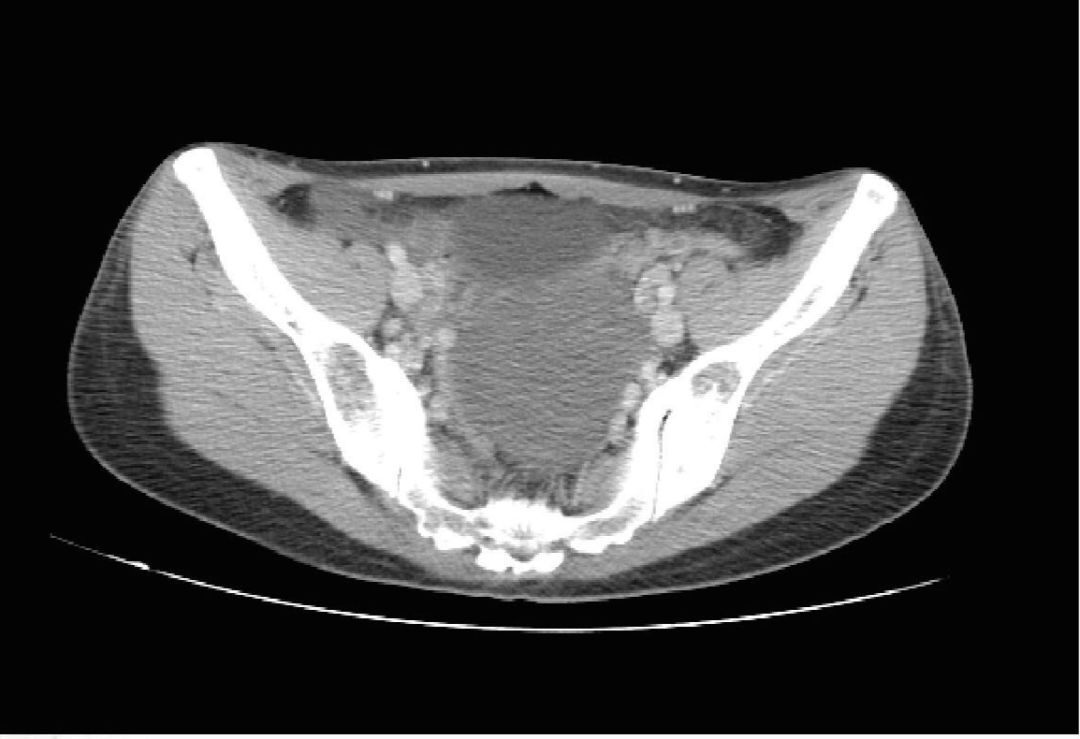

上腹部盆腔CT示: 1、胃体胃壁稍增厚,胃周可见小淋巴结,请结合临床。 2、盆腔巨大占位灶,转移瘤考虑。 3、腹盆腔少量积液。 4、胸腰椎及骨盆多发骨转移考虑。

图1  2017年5月26号CT影像